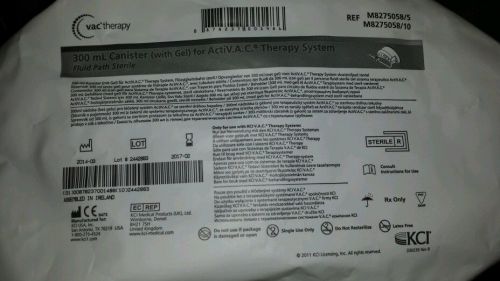

300ml Canister (with Gel) for ActiV.A.C. Therapy System KCI Wound Vac X 1